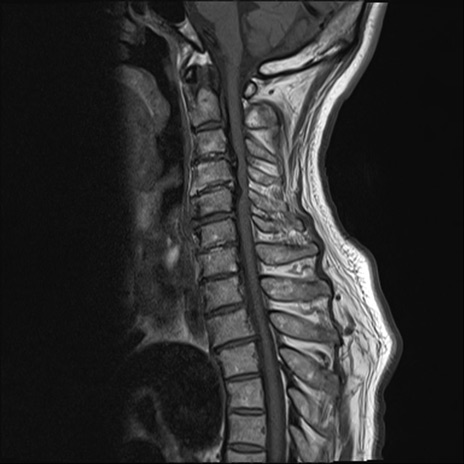

【整形】TIPS症例7 頚椎MRI T1WI(矢状断像)

頚椎MRI

T2WI(矢状断像)